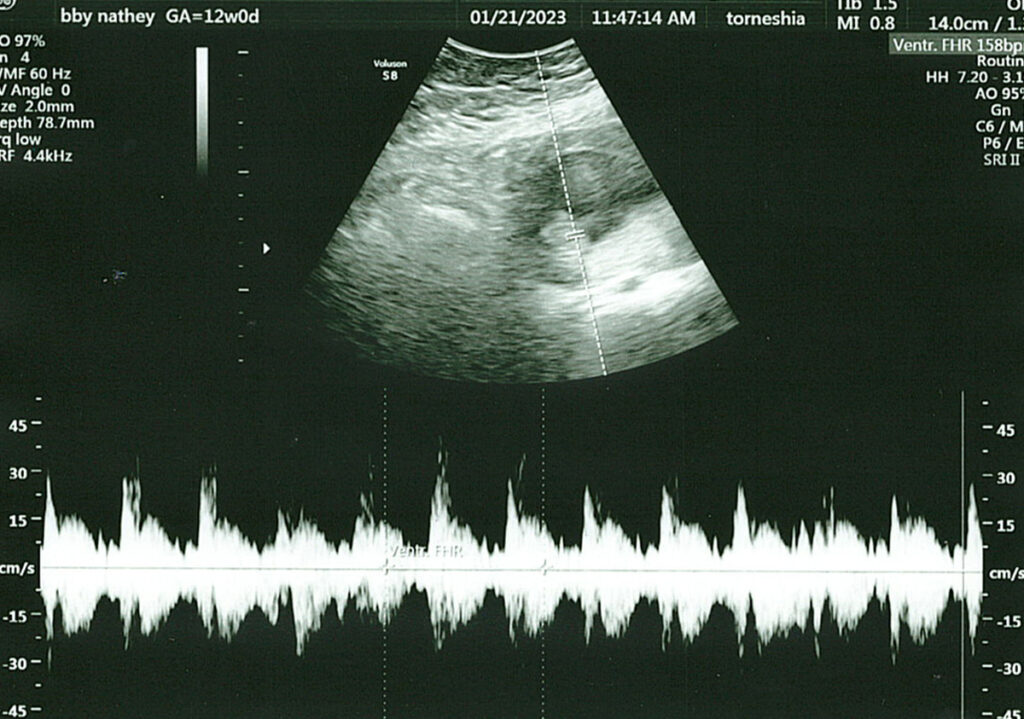

I’m happy to report the visit went amazing, and we couldn’t have asked for a better ultrasound tech. She first let us hear the heartbeat and even spent extra time with us, trying to get better photos (though I need to drink more water). She let us record the visit, and I’ve included a few pictures and a short video clip showing our baby moving around. Life is such a miracle, and seeing this baby, the size of a lime, move around was incredible.

This pregnancy – Video Clip from Our 12 Week Ultrasound

Here’s a short clip from our visit where you can see our baby moving around. This visit was exactly what we needed, and I feel even more connected to this little human, though it’s still crazy to think they’re growing inside my body.